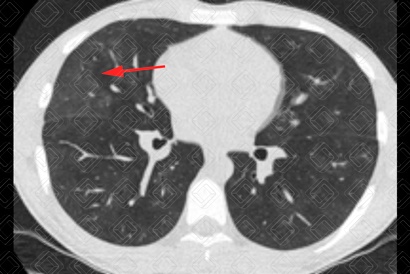

Texto alternativo para a imagem Créditos: Dra. Elazir Mota - Rio de Janeiro/RJ

Descrição das imagens: Tomografia computadorizada do tórax evidenciando tênues lesões em vidro fosco (setas vermelhas) dispersas pelo parênquima pulmonar, por hemorragia alveolar. Caso confirmado de leptospirose com apresentação pulmonar.

• Tomografia computadorizada de tórax: Opacidades em vidro fosco, pavimentação em mosaico (padrão caracterizado por áreas em vidro fosco associado a espessamento dos septos interlobulares) e consolidações são os achados mais frequentemente observados e traduzem a presença de hemorragia alveolar (uma complicação que ocorre na leptospirose), como demonstrado nas imagens acima. Sua distribuição é preferencialmente periférica, subpleural e nas regiões póstero-inferiores dos pulmões. Cabe lembrar, no entanto, que são achados de imagem inespecíficos, assim como na radiografia. O diagnóstico só pode ser sugerido diante de uma boa história clínica.